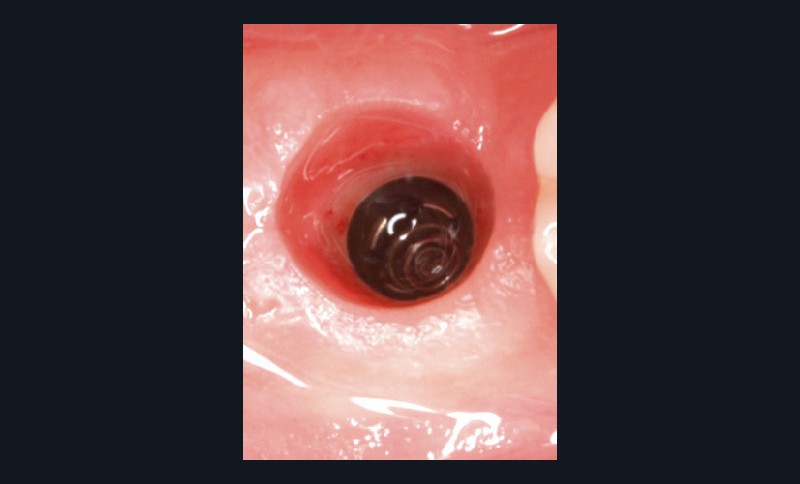

Elle se définit par défaut, se traduit cliniquement par « l’absence d’inflammation, de saignement au sondage, d’œdème et de suppuration », sans tenir compte des profondeurs de sondage [4-6] (fig. 1).